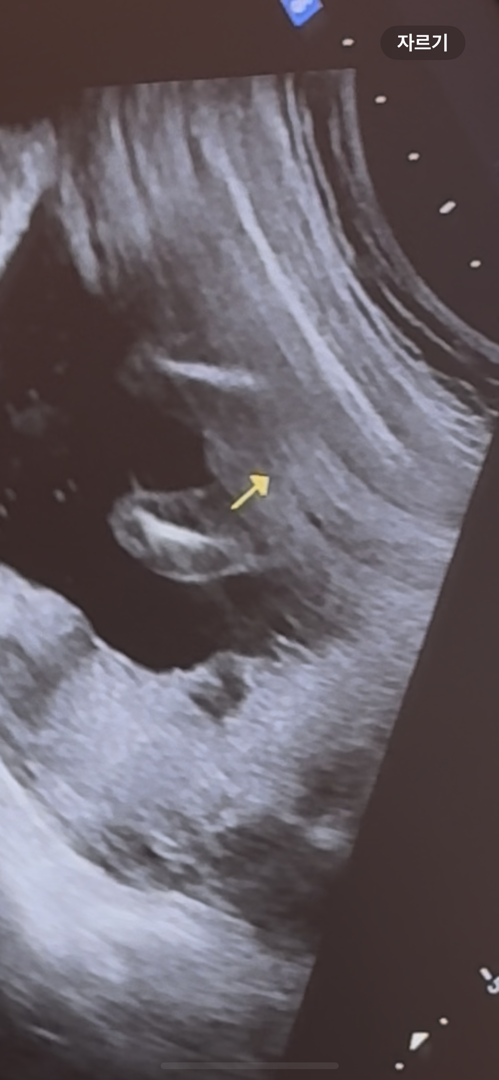

추가사진이요ㅠㅠ

딸일 확률이 높다는데 ㅠㅠ 진짜 아예 확률이 없을까요 정말 바뀌지않을까요? 19주에요